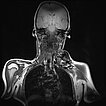

Dynamische, kontrastmittelunterstützte, zeitlich hochaufgelöste MR-Angiographie; Darstellung 46 s nach intravenöser Kontrastmittelapplikation. Das Kontrastmittel hier noch vorwiegend im kleinen Kreislauf der Lunge (Frühphase).